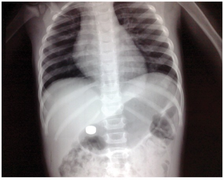

Large bowel obstruction (Cecal volvulus; black arrows).